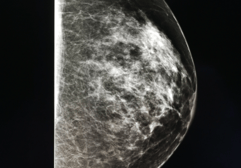

Breast density refers to the proportion of fibroglandular tissue, which is white, compared to fatty tissue, which is dark, in the breast. It can only be measured measured visually by the radiologist or via an automated computer software on a mammogram.  It cannot be measured during a clinical breast exam.

On a mammogram, both dense tissue and cancer appear white. This creates a masking black and white mammogram imageeffect, where tumors can be hidden within the fibroglandular tissue. Due to this, it is sometimes difficult to detect cancers which may delay early-stage diagnosis

"The denser the tissue, the harder it is to see what does not belong," Dr. Parris explains. "It’s like trying to find a snowball in a snowstorm."